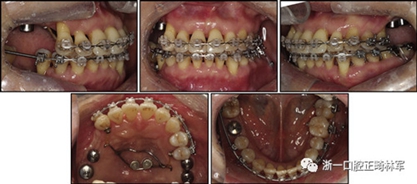

完成診斷性設(shè)計后,治療后穩(wěn)定的咬合是確定的(圖5)。進行治療之前,治療計劃和順序需要通過涉及正畸,牙周病和修復(fù)的多學(xué)科綜合治療方法加以確認(圖6)。牙周治療應(yīng)在正畸治療前完成。牙周疾病的治療采用全口潔治,上頜和下頜前牙區(qū)的刮治術(shù),以及下頜左側(cè)后牙區(qū)的翻瓣手術(shù)。休息3個月后,幾乎每個部位都實現(xiàn)了牙周袋深度縮小,探針出血幾乎沒有(表III)??刂蒲装Y后,開始正畸治療。在正畸治療期間定期進行牙周維護的復(fù)診檢查。

拔除下頜左側(cè)側(cè)切牙,除了4顆前牙外,下頜和上頜牙齒通過0.022英寸的Clippy-C裝置(日本東京的Tomy)粘接聯(lián)合。磨牙管粘結(jié)在下頜磨牙上。排齊過程從0.014英寸的鎳鈦弓絲開始,然后是0.016英寸的鎳鈦弓絲。為了美觀,在拔除的下頜左側(cè)側(cè)切牙間隙中放入一個修復(fù)體。為了防止牙齒的圓形轉(zhuǎn)動,4根上頜前牙被繞過,使牙齒能在尖牙被推向遠中后排齊。將兩個TADs(Orlus,Ortholution,Seoul,Korea)放置在腭板,并且有鉤子附著。將一小段0.016英寸的不銹鋼弓絲放置在上頜左側(cè)尖牙和前磨牙上,并且通過附著在腭板上的鉤子將上頜尖牙和左側(cè)前磨牙推向遠中。

對于近中傾斜和過度萌出的上頜右側(cè)尖牙,需要控制牙齒向遠中傾斜和向下推入。用兩個鉤子在兩側(cè)施加不同方向的力,以期望右側(cè)尖牙的推入(圖7)。在上頜尖牙遠中移動后,用一根0.014英寸的鎳鈦弓絲將4顆上頜前牙排齊。放置逐漸變硬的弓絲,直到上下兩個牙弓都放置0.017*0.025英寸的不銹鋼弓絲。然后關(guān)閉下頜前牙區(qū)間隙,用完全相同的力學(xué)原理將上頜全牙列向遠中移動,以獲得適當(dāng)?shù)母埠虾透采w。此外,還有一個0.017*0.025英寸β-鈦絲的直立彈簧應(yīng)用于下頜右側(cè)第二磨牙。當(dāng)直立彈簧接合到主弓絲上時,引起前磨牙的推入,第二磨牙的推出,前磨牙的頰側(cè)傾斜以及第二磨牙的舌側(cè)傾斜,以矯正牙弓形態(tài)(圖8)。

由于患者有多個缺失的后牙,因此考慮到具有垂直方向的喪失。然而,她在拔除后牙后立即去正畸科就診。她封閉了天然的左側(cè)前磨牙,并且沒有前牙的咬合磨損。因此,垂直維度被維持是確定的。在正畸治療過程中,牙種植體植入在上頜后牙區(qū)和下頜右側(cè)第一磨牙的位置(圖9)。經(jīng)過3個月的骨結(jié)合后,種植體用臨時冠修復(fù)以支持垂直維度。

圖9. 上頜牙齒推向遠中,糾正下頜左側(cè)磨牙的傾斜度,并放入種植體

在患者適應(yīng)了垂直維度和咬合后,裝置被去除(圖10)。主動治療時間為17個月。牙列立即用固定的保持器進行保持,保持器從下頜一側(cè)前磨牙到另一側(cè)前磨牙,以及從上頜一側(cè)前磨牙到另一側(cè)前磨牙的臨時牙冠上。此外,真空成型的保持器應(yīng)用于上下兩個牙弓?;颊弑晦D(zhuǎn)診給修復(fù)??漆t(yī)生進行進一步的修復(fù)手術(shù),還轉(zhuǎn)診給牙周病專家進行維護和隨訪。在最終確認她的穩(wěn)定咬合和適應(yīng)后,進行最終修復(fù)體修復(fù)。